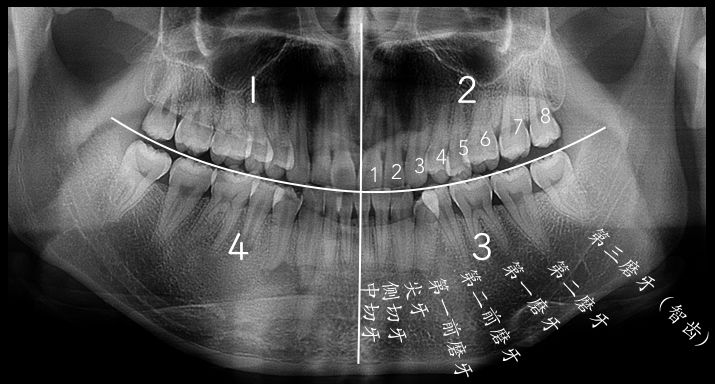

智齿是从正中的门牙往里数第八颗牙齿,也就是第三颗磨牙。它是发育、萌出最晚的牙齿,通常在4~5岁时形成牙胚,随后逐渐发育形成牙齿,一般17~25岁左右萌出,此时人的生理、心理发育都接近成熟,因此俗称“智齿”。

智齿的形态也是各种各样,基本罗列如下几种,实际会有更多复杂情况。